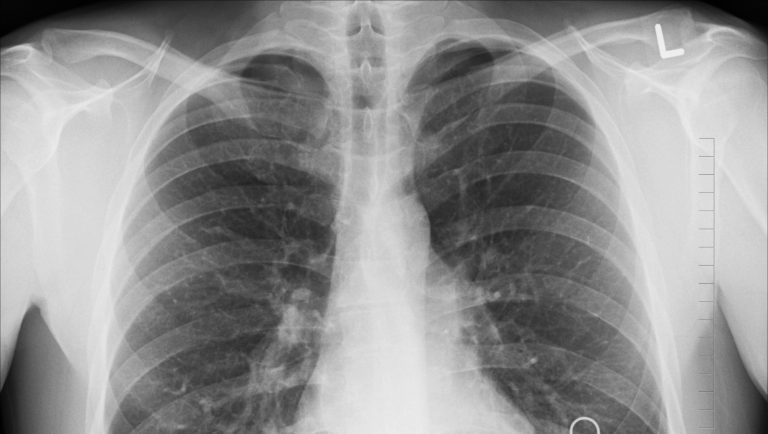

tüdő